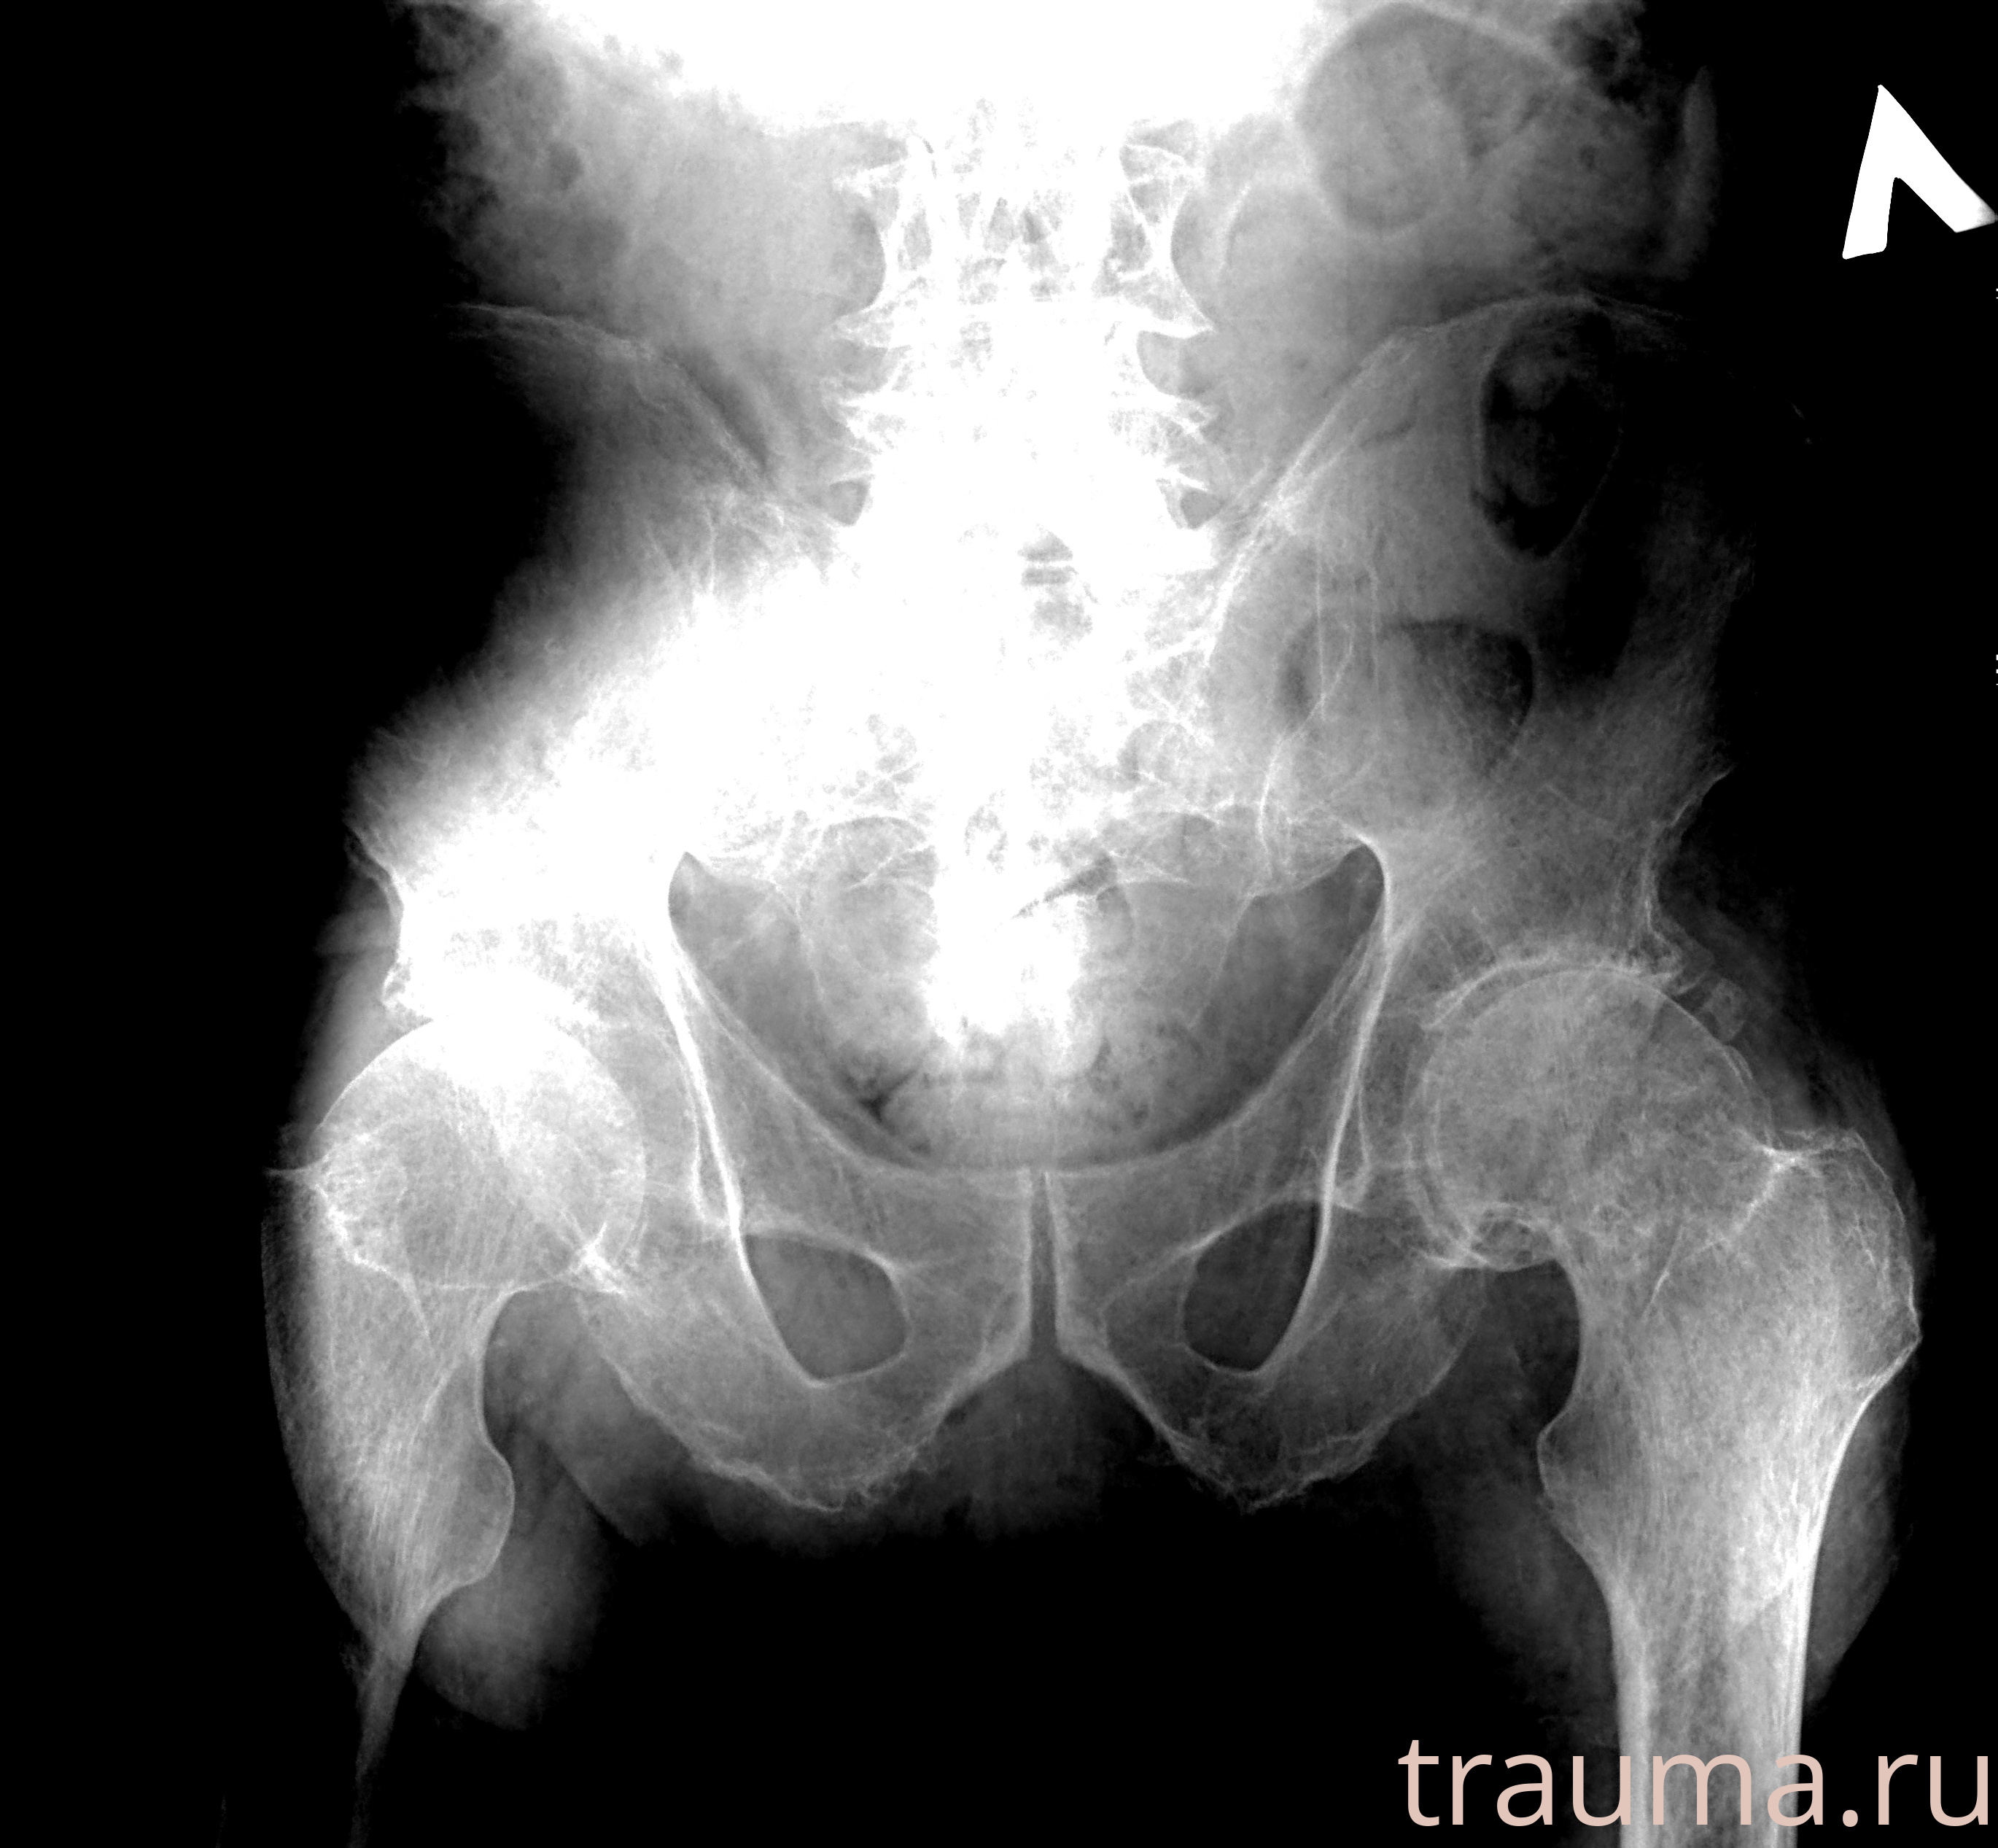

Рентгенограммы

Рентген на дому: по вашему адресу приезжает врач-рентгенолог, травматолог-ортопед с мобильным рентгеновским аппаратом, проводит диагностику травмы или заболевания, делает необходимые рентгенограммы, дает рекомендации по дальнейшему лечению. Получить качественные снимки в домашних условиях возможно благодаря уникальной методике, разработанной МосРентген Центром для института  Склифосовского